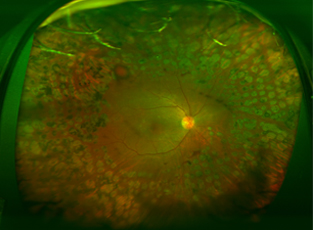

광학촬영·망막정맥폐쇄